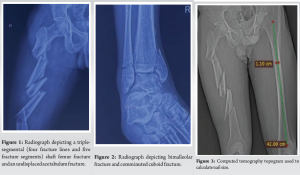

A 34-year-old male was brought to our emergency department following a high-energy road traffic accident. The patient’s complaints included severe pain, swelling, and an inability to bear weight on his left lower limb. Upon clinical examination, the left thigh had considerable soft tissue swelling and localised tenderness. Despite having stable vital signs, he appeared distressed due to the pain and swelling. X-rays of the left thigh revealed a triple-segmental shaft femur fracture (Fig. 1). This is an uncommon pattern–the femur is divided into five segments. Additional imaging revealed a bimalleolar fracture, a comminuted cuboid fracture, an undisplaced acetabulum fracture, and an undisplaced patella fracture (Fig. 2).

In this case, a computed tomography (CT) topogram/scout view/scanogram was utilised to accurately assess the femoral anatomy and determine the appropriate size for the intramedullary nail [5-7]. We measured the diameter and length of the femoral canal, ensuring precise selection of the nail size (Fig. 3). A 3D CT reconstruction was also done to aid surgical planning (Fig. 4 and 5).